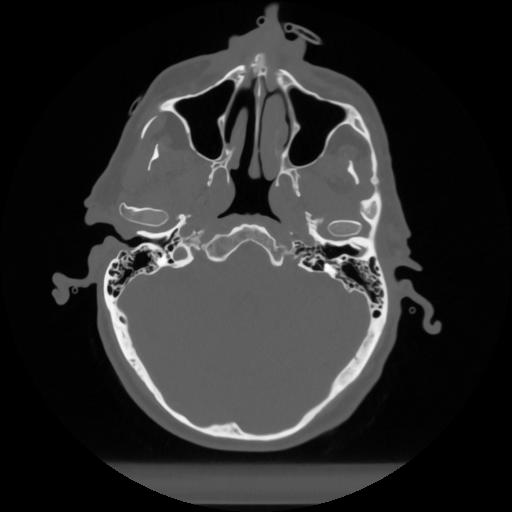

12 P.BLANDAS,,Vol,0.5,P.BLANDAS,,